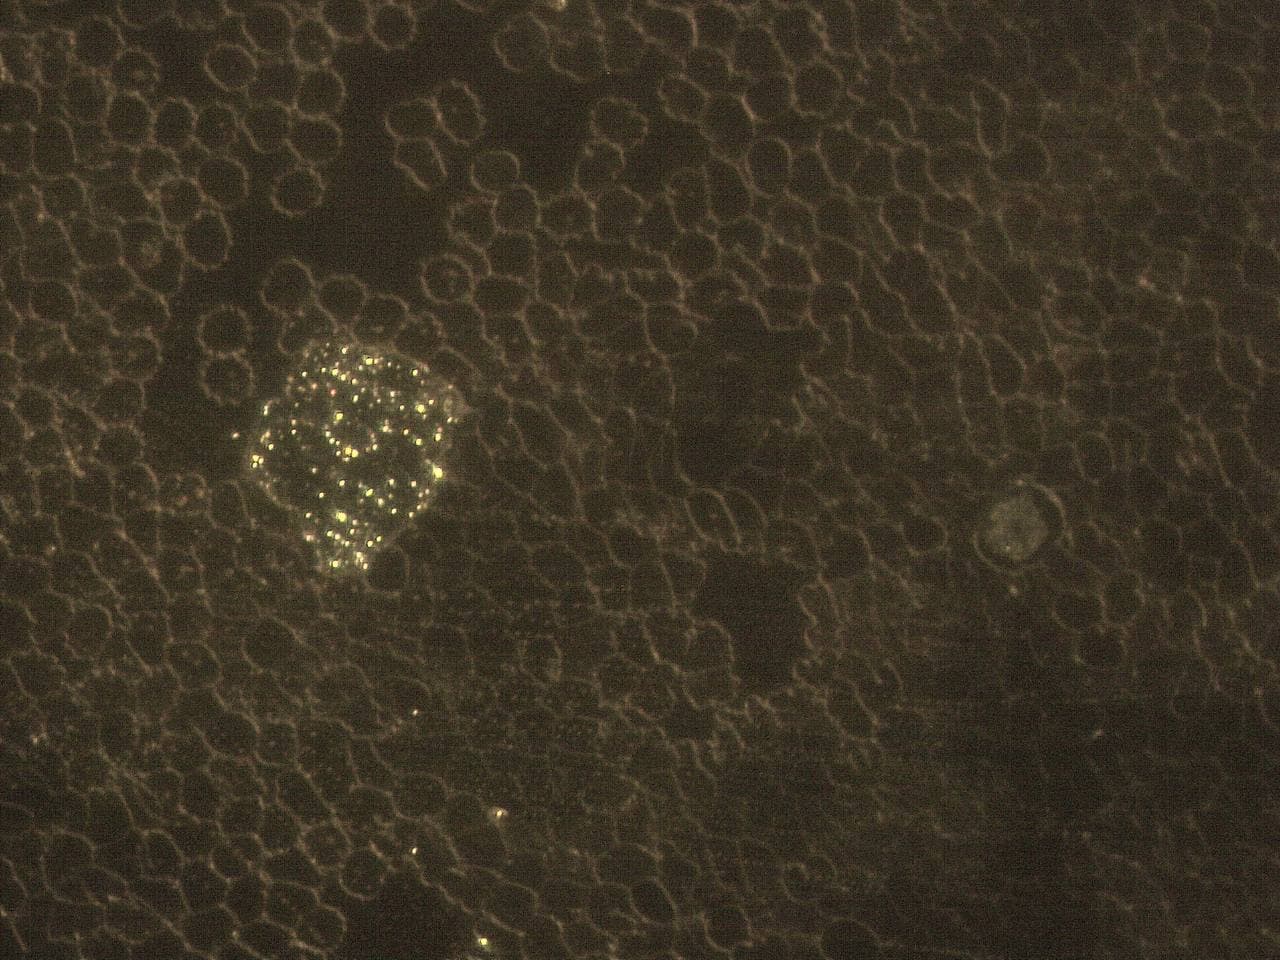

GENimpfschaden

im Blutbild 15.9.2021: Foto 3

Impfschäden Schweiz Coronaimpfung, [15.09.21

13:19]

https://t.me/Impfschaden_Corona_Schweiz/21524

[Weitergeleitet aus Holger Fischer Rechtsanwalt

(Maya Stella)]

Seltsame Form über den Erys

GENimpfschaden im Blutbild 15.9.2021: Foto 3

[39] |

GENimpfschaden

im Blutbild 15.9.2021: Foto 4

Impfschäden Schweiz Coronaimpfung, [15.09.21

13:19]

https://t.me/Impfschaden_Corona_Schweiz/21525

[Weitergeleitet aus Holger Fischer Rechtsanwalt

(Maya Stella)]

Seltsame Form im Blut Erys wirken wie tot

GENimpfschaden im Blutbild 15.9.2021: Foto 4

[40] |

GENimpfschaden

im Blutbild 15.9.2021: Foto 5

Impfschäden Schweiz Coronaimpfung, [15.09.21

13:19]

https://t.me/Impfschaden_Corona_Schweiz/21526

[Weitergeleitet aus Holger Fischer Rechtsanwalt

(Maya Stella)]

Stechapfelformen

GENimpfschaden im Blutbild 15.9.2021: Foto 5

[41] |

GENimpfschaden

im Blutbild 15.9.2021: Foto 6

Impfschäden Schweiz Coronaimpfung, [15.09.21

13:19]

https://t.me/Impfschaden_Corona_Schweiz/21527

[Weitergeleitet aus Holger Fischer Rechtsanwalt

(Maya Stella)]

spitze Gebilde

GENimpfschaden im Blutbild 15.9.2021: Foto 6

[42]